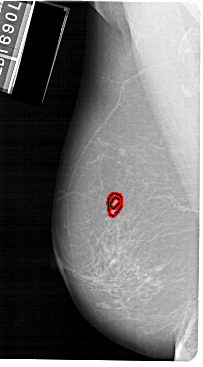

A_1149_1.LEFT_CC

LEFT_CC LINES 5491 PIXELS_PER_LINE 3061 BITS_PER_PIXEL 12 RESOLUTION 43.5 OVERLAY

FILE: A_1149_1.LEFT_MLO.OVERLAY

TOTAL_ABNORMALITIES 1

ABNORMALITY 1

LESION_TYPE MASS SHAPE IRREGULAR MARGINS SPICULATED

ASSESSMENT 4

SUBTLETY 2

PATHOLOGY MALIGNANT

TOTAL_OUTLINES 2

BOUNDARY

CORE